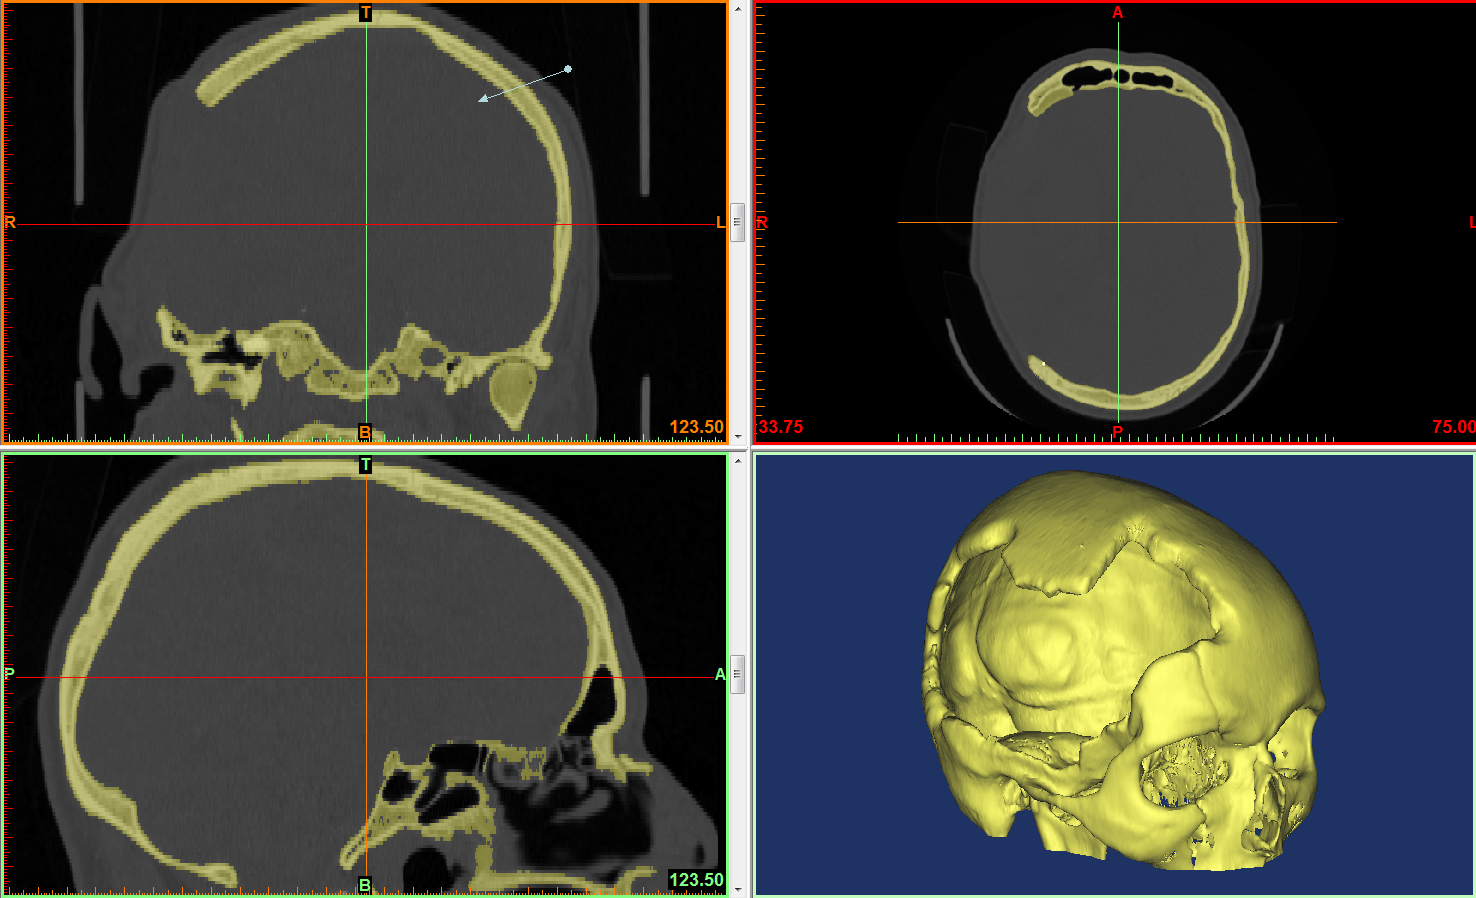

Кт колизей: оригинальные изображения, которыми можно не только наслаждаться, но и делиться с друзьями и скачивать совершенно бесплатно

Кт колизей: оригинальные изображения, которыми можно не только наслаждаться, но и делиться с друзьями и скачивать совершенно бесплатно